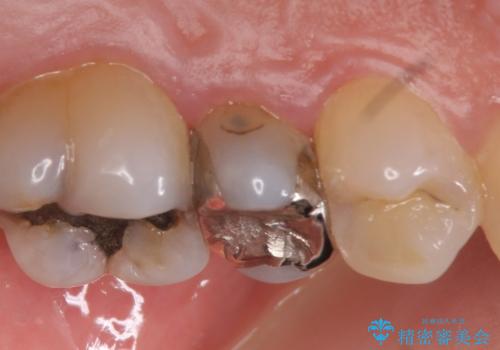

- 左上の奥歯がズキズキ痛むので診て欲しいといらっしゃった方の症例です。

診査の結果左上5、6番の歯が痛みの原因であり、神経の保存が難しかったため根管治療を行いました。

痛みの消失を確認後、オールセラミッククラウンによる補綴を行いました。